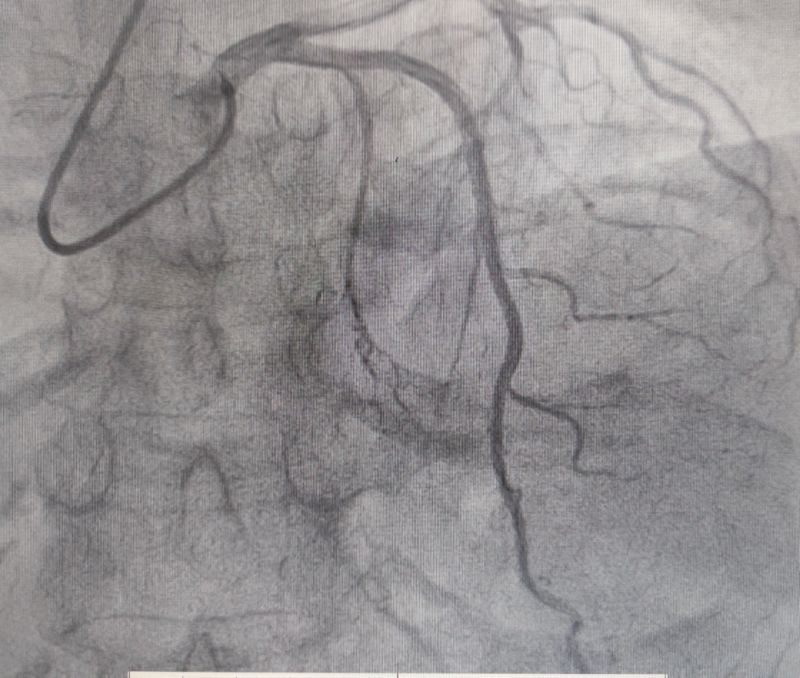

测压

消融时测压

经过多轮严谨的术前讨论,在吴栋梁院长的专业指导下,崔旭辉主任医师团队决定在临时起搏器的安全保护下,为患者实施冠状动脉造影术及室间隔化学消融术。术中,团队通过造影精准锁定第一穿隔支为消融靶血管。测压数据显示:左室压260/15mmHg,流出道173/6mmHg,主动脉压106/70 mmHg,压力阶差达87mmHg。随后,团队使用2.0X15mm预扩球囊以8atm压力阻断第一穿隔支远端血流1分钟,再次测压时,压力从269/7mmHg骤降至174/4mmHg,这一结果充分证实该血管正是室间隔的有效供血血管。紧接着,团队通过SPRINTER OTW2.0×8mm球囊缓慢注入1.4ml无水酒精。10分钟后复测,左心室压降至136/5 mmHg,主动脉压为112/93 mmHg。术后第2天,王女士胸闷、气短、心悸等不适症状完全消失。复查心脏彩超显示:EF值与FS值保持稳定,收缩期左室流出道血流速度降至252cm/s,PG值为25mmHg。